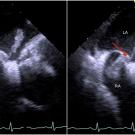

Transesophageal echocardiography demonstrated thrombi in transit through a patent foramen ovale and showed the presence of thrombi in all 4 chambers of the heart.